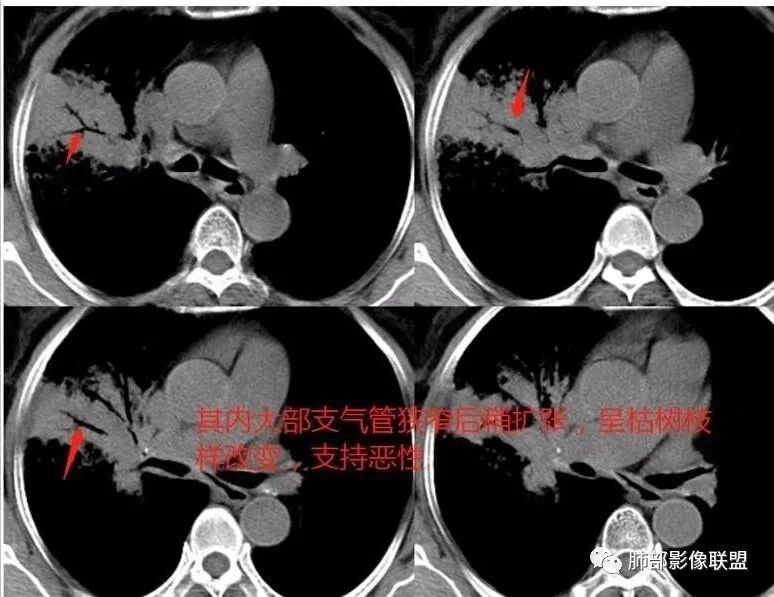

右肺上叶大片状阴影,内见僵硬的支气管,部分支气管轻度扩张,内见一空洞和液平,病灶边缘可见磨玻璃影,首先考虑恶性病变,粘液性腺癌伴感染可能。

老年女性,慢性病史,白色痰液,量多,病灶起于胸膜下,实性加磨玻璃,磨玻璃边缘偏轻,跨叶生长,病灶内可见枯树枝,考虑肺炎型肺癌。

老年女性,右肺上叶大片实变及磨玻璃密度影,磨玻璃边缘清晰,内可见小叶间隔增厚,内可见空洞,似可见分隔,叶间裂局部膨隆,纵膈窗,没有增强,枯树枝不明显,肺炎型肺癌可能,鉴别大叶性肺炎,结核?

胸CT:右肺上叶实变内可见支气管充气征,近端支气管狭窄,远端扩张,周围可见毛玻璃影,右肺中叶支气管闭塞,并可见气道壁钙化,右肺中叶体积缩小,实变内可见空洞,并可见气液平面,空洞周围可见毛玻璃样影,右肺下叶支气管开口狭窄,右肺门淋巴结肿大。纵隔窗可见病灶与壁层胸膜间隙增宽,考虑良性病变-----感染性病变------TB?

老年女性,右肺中上叶病灶,血象不高,血沉高,TB dna阴性,上叶尖端病灶,紧贴胸膜,边界似清非清,中间可见实变,内见枯树枝征,首先考虑粘液腺癌可能性大。患者右肺中叶见空洞、气液平,病灶没多发空洞,可见气液平,考虑合并TB感染。

老年女性,无诱因咳嗽咳痰,白色粘液痰,抗炎治疗无好转,右肺多叶磨玻璃影,其内见枯树枝征,磨玻璃边界清,中间见实变影,且部分实变影内见空洞或局部支气管扩张,内壁光整,无纵隔淋巴结肿大,常规考虑粘液性腺癌,感染性病变待排,细菌性的排除,白细胞不高,不太支持,建议支气管镜检。

1.右上肺大片状影,周围有磨玻璃影,支气管截断征、枯枝征、远端支气管充气征,可见多个大小不等囊泡(支气管阻塞活瓣作用形成),病灶有少许收缩力感,叶间裂被稍牵拉内移;

依据:老年,病史月余,不发烧,以咳嗽咳白痰为主,相关感染指标WBC丶CRP基本上正常,抗生素无效,不支持CAP,无免疫下降,不支持曲霉(支气管肺炎型),非典亦不支持。CT肺内实变,周边GGo,胸膜下丶由外向内发展,常规考虑粘液腺丶OP丶PC丶病毒,病史排除病毒,有枯树枝丶空洞,常规不支持OP丶PC,

病史老年女,白痰;影像实变,ggo多数边界清,病灶下缘部分不清,枯树枝,支气管近端阻塞、僵硬,病灶跨叶;病灶内空洞,有液平;间质增厚有结节感;肺炎型肺癌大于干酪性肺炎。

老年女性,慢性病程,咳嗽伴白色粘液痰,无发热腹痛,糖尿病,白细胞及C反应蛋白不高,血沉快,铁蛋白高。胸部CT,右肺上叶大片状实变伴磨玻璃密度影,边界不清,边缘局部膨隆,叶裂弧形下坠,实变影宽基底与胸膜相贴;右肺下叶前基底段见类似病灶;右肺中叶不张并空洞形成,空洞内见气液平面;综合考虑右肺上叶及下叶肺炎型肺癌,右肺中叶结核。

白色粘液痰,枯树枝,支气管僵直,有空洞,磨玻璃,叶间裂膨隆、下坠,吴婧老师的肺炎型粘液性腺癌十大特点中占了好多条,所以考虑粘液腺癌,就差增强看看强化如何,血管如何了

薄厚不均匀,枯树枝,支气管壁僵直,叶间裂膨隆,白色粘液痰,肿瘤标志物增高,考虑粘液肺癌可能。

老年女性,咳白色粘液痰,右肺跨叶大片高密度影,密度不均匀,其内见支气管枯树征,有空洞,边缘部分清楚,叶间裂有下坠膨隆感。考虑粘液腺癌,鉴别干酪性肺炎

我觉得这个长轴和支气管平行,不是和胸膜平行。不是起源于胸膜下,病灶比较密实,内部粘液密度不多,这是不符合地方。当然也有很恶性的特点,

这些层面的支气管我觉得像结核的狭窄后扩张,